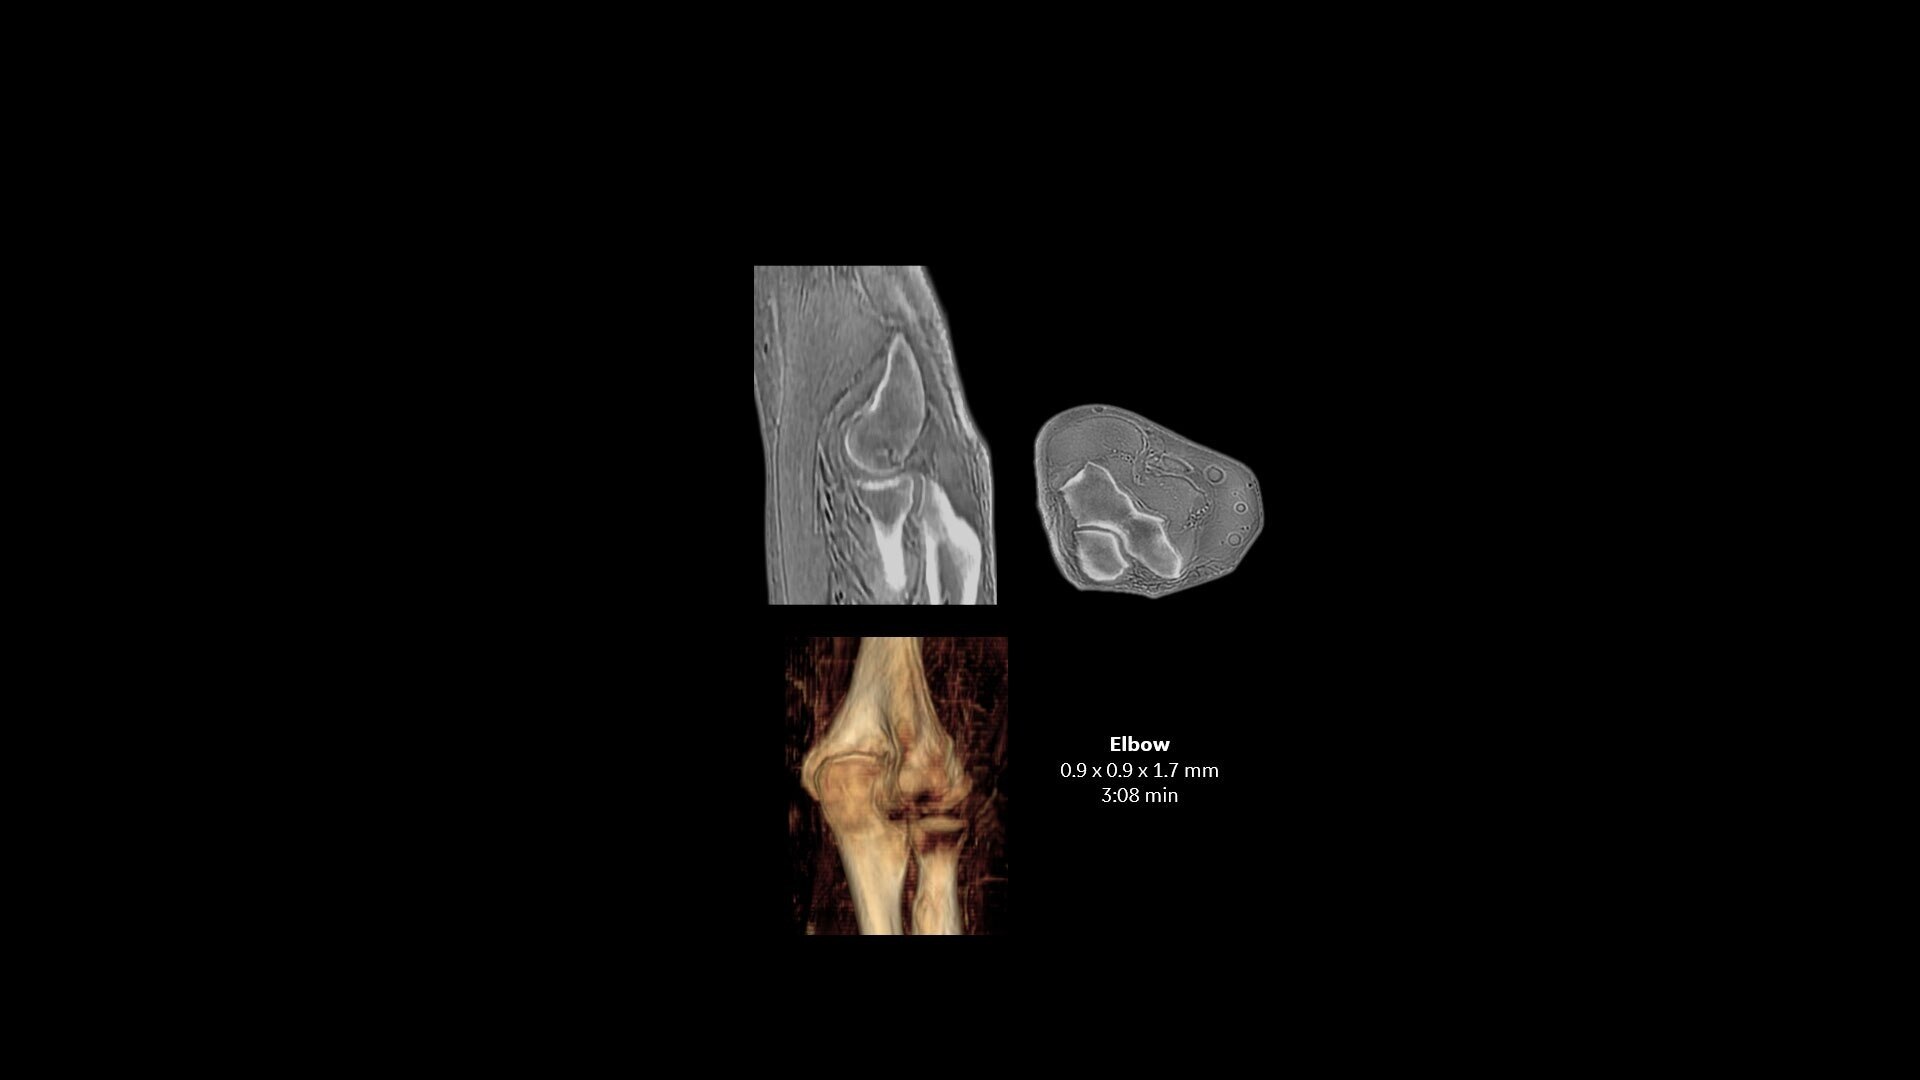

Available for all anatomies without ionizing radiation, oZTEo delivers images of bone morphology, calcification, ossification and fractures. oZTEo complements conventional MR soft tissue exams with perfect co-registration and provides 3D isotropic imaging using a radial ZTE acquisition, with inherent motion insensitivity. Use oZTEo with Volume Illumination for realistic 3D rendering.

When oZTEo is included in an MR exam, cortical bone information is perfectly co-registered with the soft tissue series, making it a one-stop imaging shop for most routine MSK needs.